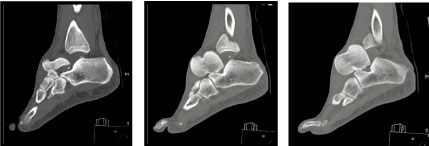

Plain radiographs showed a posterolateral dislocation of talus with a medial malleolus fracture (Figure 2). CT scans showed a tri-articular dislocation with total extrusion of the intact talus from the tibio-talar, talo-calcaneal and talo-navicular joints (Figure 3). There was an associated displaced medial malleolar fracture but no other occult fractures or intra-articular fragments (Figure 4).

Figure 2: Antero-posterior and lateral radiographs of total lateral talar dislocation. View Figure 2

Figure 3: CT sagittal view: Total talar dislocation (TTD) with dislocation of sub-talar, talonavicular, and tibiotalar joints. View Figure 3

Figure 4: CT coronal view of the foot showing an associated medial malleolar fracture. View Figure 4